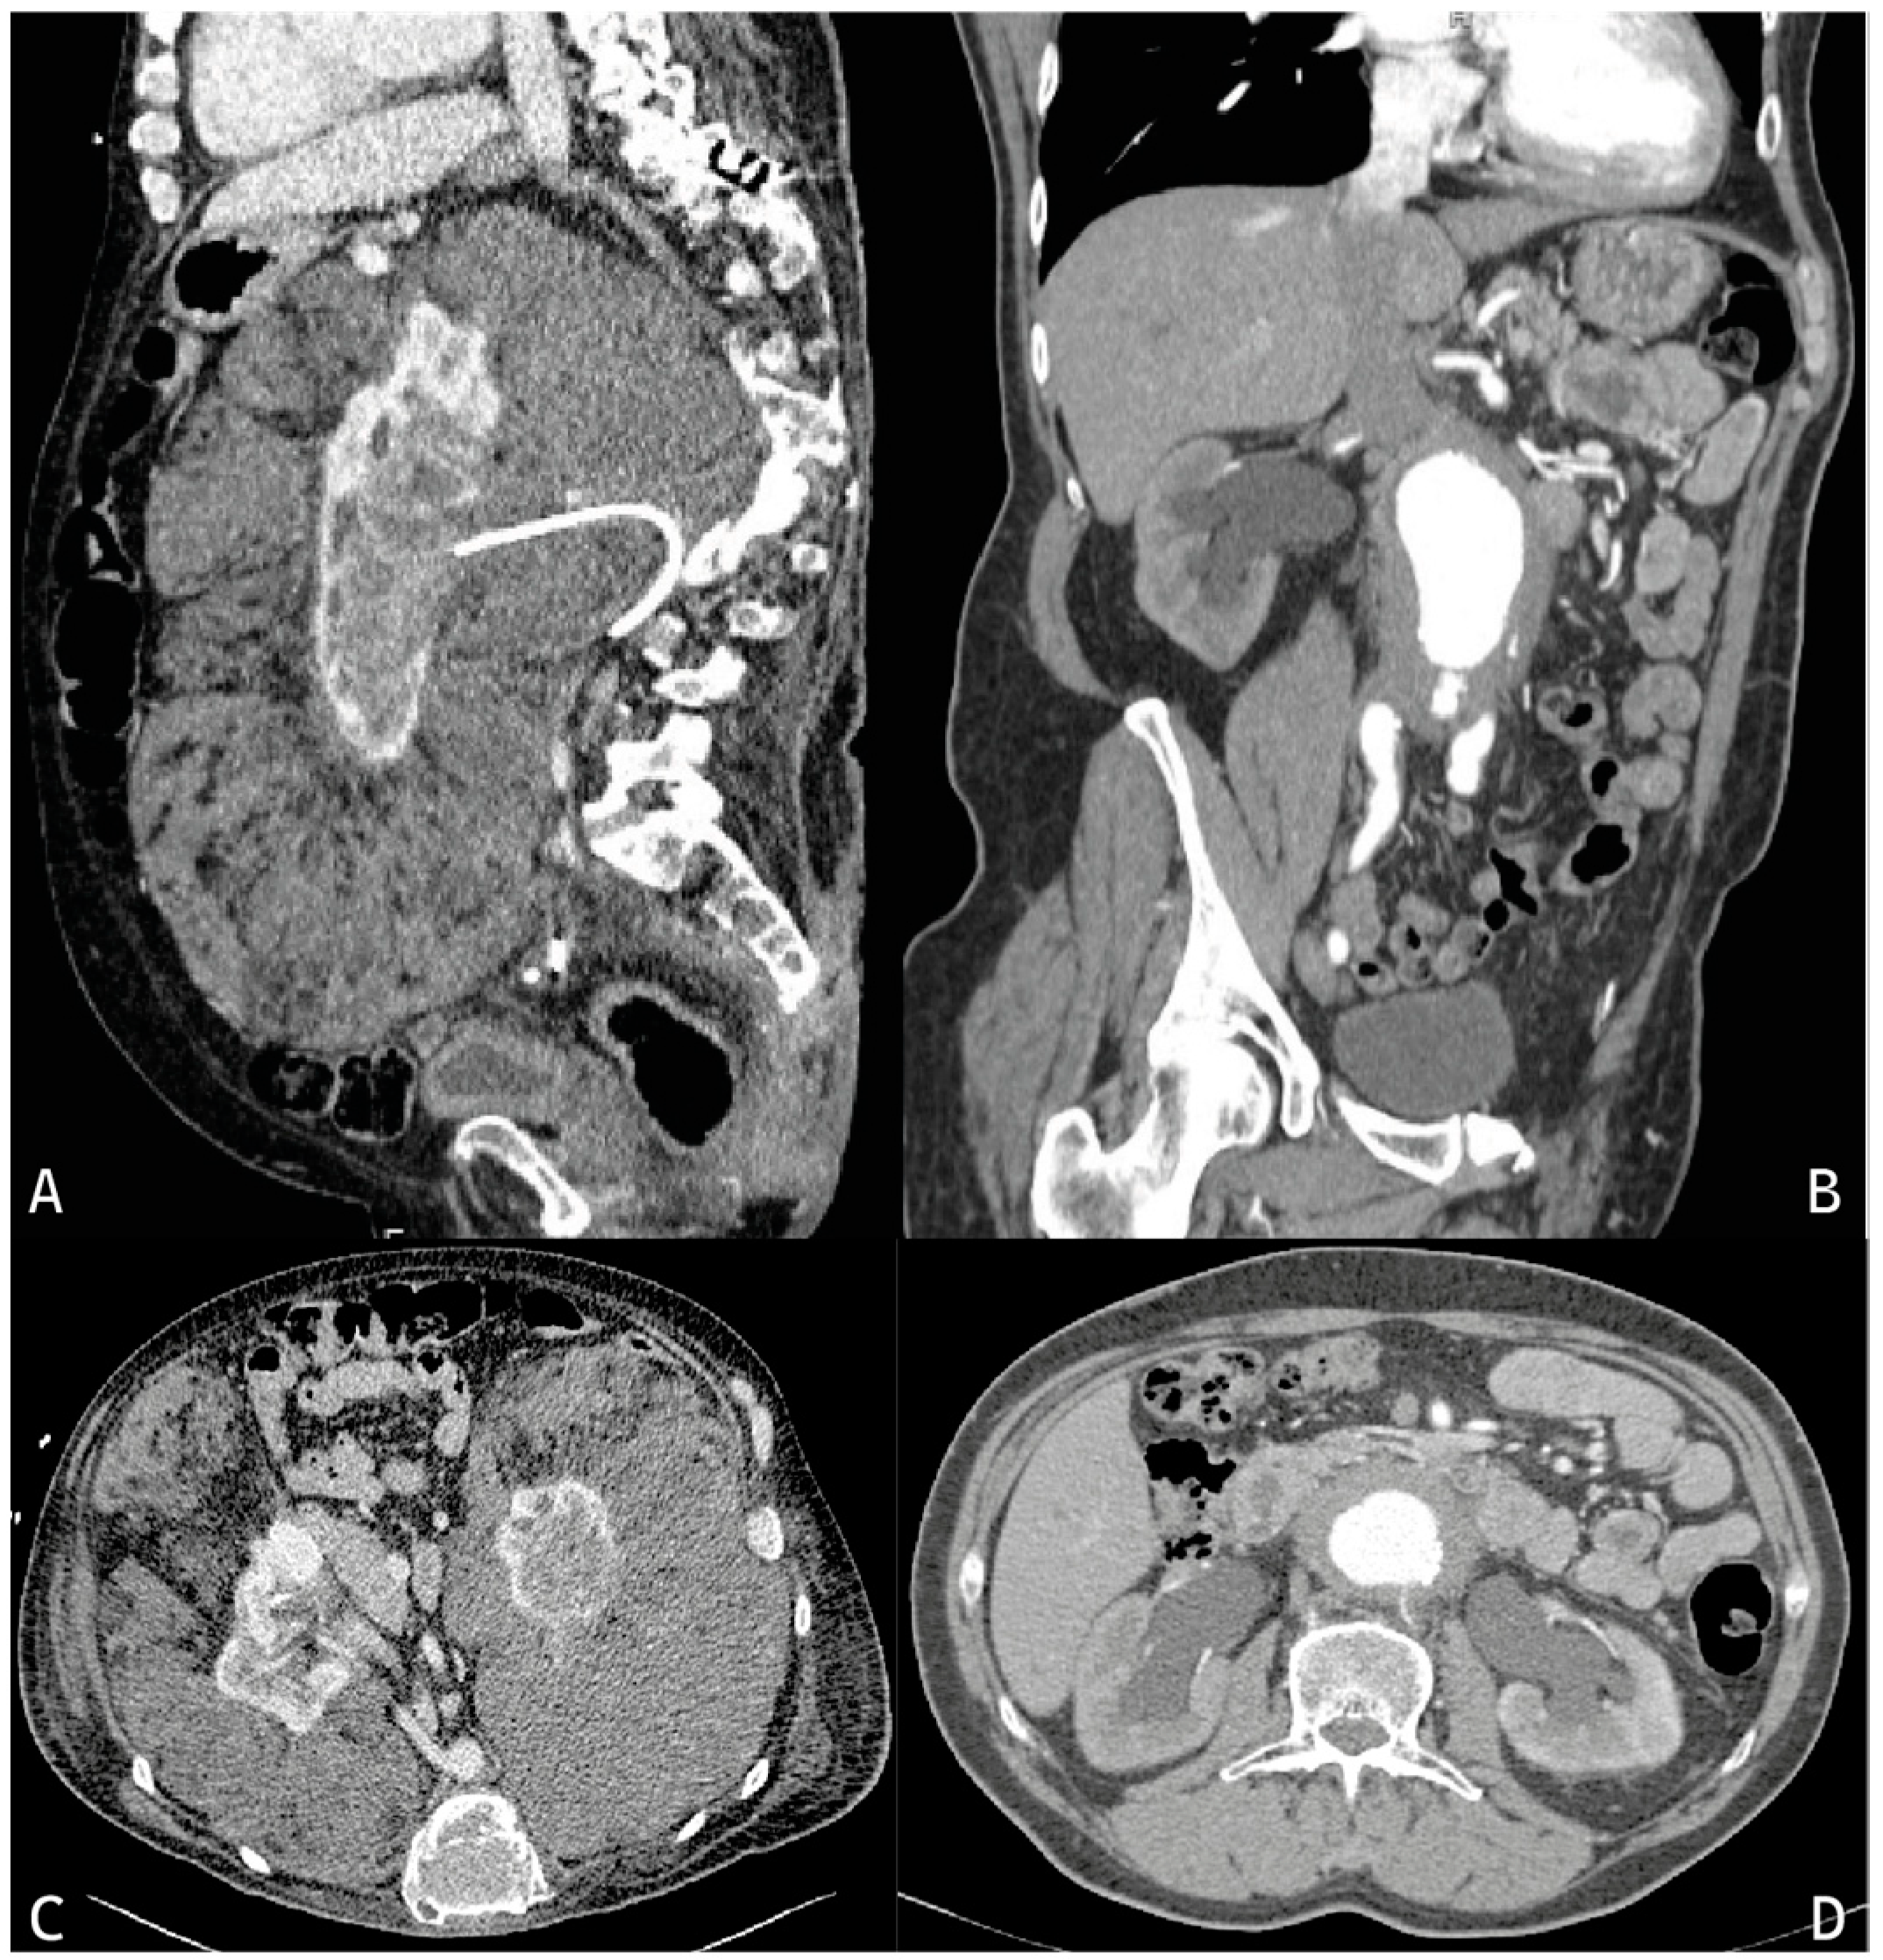

Figure 1.

Computed tomography images of idiopathic retroperitoneal fibrosis and Erdheim–Chester disease. (A): Sagittal scan showing a kidney (with a ureteral stent) completely enclosed by fibrotic tissue. In (C), a transversal scan of the same patient shows that both kidneys are enclosed and compressed by extrarenal fibrosis, typical of Erdheim–Chester disease. In (B,D), sagittal and transversal scans, respectively, of retroperitoneal fibrosis are shown, with ureteral compression and therefore ureteral enlargement (hydronephrosis) with periaortic fibrotic tissue. The abdominal aorta is also aneurysmatic, configuring a peculiar “variant” of idiopathic retroperitoneal fibrosis referred to as “perianeurysmal [aortic] fibrosis” by some authors.

Computed tomography (CT) and magnetic resonance imaging (MRI) are required for the diagnosis of IRF and its staging. CT scans show homogeneous tissue, hysodense to muscle, and MRI shows hypointense tissue in T1-weighted scans (Figure 1). Moreover, MRI T2-weighted scan intensity correlates with the degree of inflammatory disease activity. Contrast enhancement, both in CT and MRI, also correlates with disease activity. However, fluorodeoxyglucose-positron emission tomography (FDG-PET) remains the gold standard for assessing disease activity at diagnosis and during follow-up, proving to be even more sensitive and specific than the common indices of serum inflammation [54]. Imaging (associated with specific laboratory investigations and clinical picture of the overall patient) also plays a fundamental role in the differential diagnosis with other pathologies (autoimmune, infectious, neoplastic disease), which must be ruled out [48].

When retroperitoneal involvement is present, as in RPF, TC and MRI are gold-standard imaging techniques. The pathological mass appears hysodense on unenhanced CT scans and slightly hyperdense on enhanced CT scans and isointense to muscle on MRI in both T1 and T2W scans and mild hypertense on enhanced MRI (Figure 1) [58]. Different from RPF, the aorta is completely (thoracic, abdominal aorta, and its branches) and circumferentially involved in ECD (“coated aorta”) [14]. In addition to the great retroperitoneal vessels, the other frequently involved structures are the kidneys, which may present a perirenal fat infiltration and capsular thickening, with a suggestive appearance frequently referred to as “hairy kidneys”. The renal sinus is frequently involved. Ureters are often encased in their upper portion, causing stenosis and hydroureteronephrosis in 6% of cases of ECD, with postrenal kidney injury. Perirenal vascular peduncle involvement is also reported (“coated renal artery”) with possible but very rare severe stenosis at the proximal portion of the renal artery with consequent renovascular hypertension [59]. Contrast medium is preferable for delineating vascular structures to exclude other pathologies that enter the differential diagnosis with ECD (e.g., other forms of chronic periaortitis or histiocytosis) and is necessary for the study of CNS and sella turcica. Ultrasound remains a useful first-line investigation to identify hydronephrosis (useful for placing an immediate indication for placement of a ureteral stent or nephrostomy or ureterolysis to prevent progression of renal damage), to study renal parenchyma (measuring renal volume, cortical thickness, etc.), and to calculate resistance indices and study renal vessels flow via the Doppler method. Cardiac MRI or echocardiogram are used to detect any cardiac involvement [54].